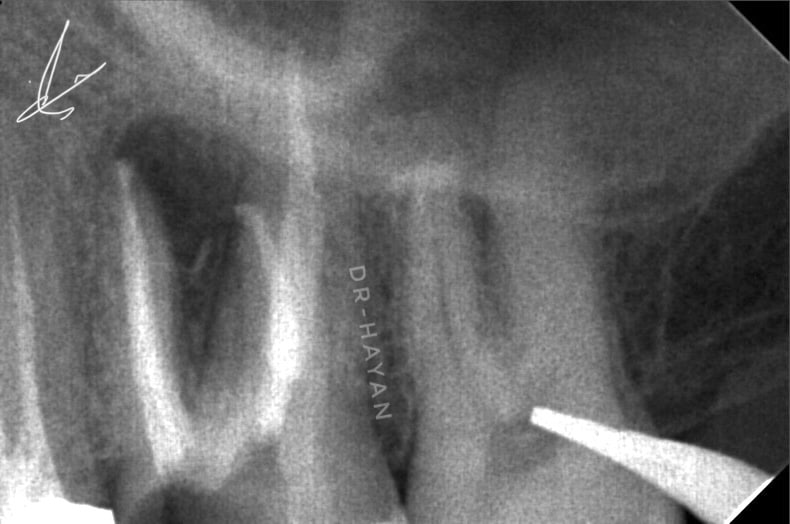

Initial view : 27 years old man suffered from sharp pain related to upper posterior area

CBCT Showing large peri apical lesion related to bad endodontic treatment upper 6 and missing mb2

Peri apical x-ray